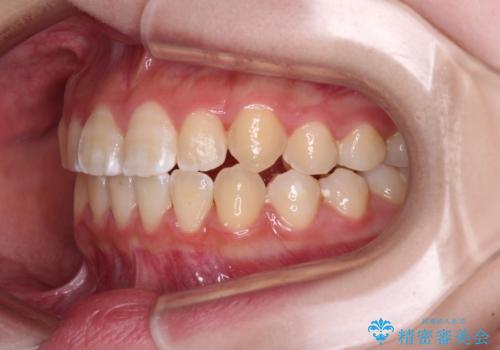

- 前歯のデコボコと磨きにくい奥歯を気にして来院された患者様です。

左右ともに上顎第二大臼歯が外側に転位しており、大変磨きにくくなっているため、補助装置により内側に引き込むことで改善することとしました。

外側を向いていた奥歯は比較的早い時期に歯列に収まり、咬み合わせも磨きやすさも改善することができました。

歯列は元々悪くなかったので、1年ほどで治療を終えることができました。